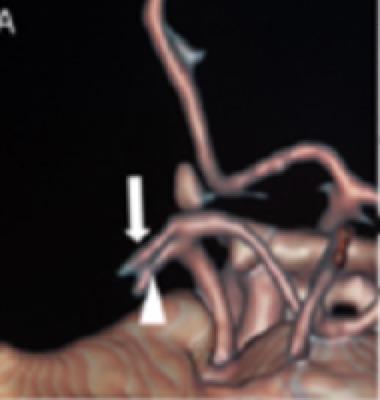

头颅CT平扫未发现右侧大脑中动脉分布区片状低密度影,阿尔伯塔省脑卒中计划早期CT缺血评分(ASPECTS)为7分。头颈血管CTA成像显示右侧颈动脉球部动脉夹层和右侧AMCA的串联闭塞,仅存双支动脉的近端残端 (图1A)。

虽然ACE60和ACE68的远端内径(ID)受到影响(分别为0.060英寸和0.068英寸),但这确保了最佳的吸入力和较少的导管穿行过程中血管损伤的机会。由于起源于大脑前动脉的一支大脑中动脉会形成豆纹动脉(图1C),因此首先处理该支大脑中动脉,随后处理另一支。